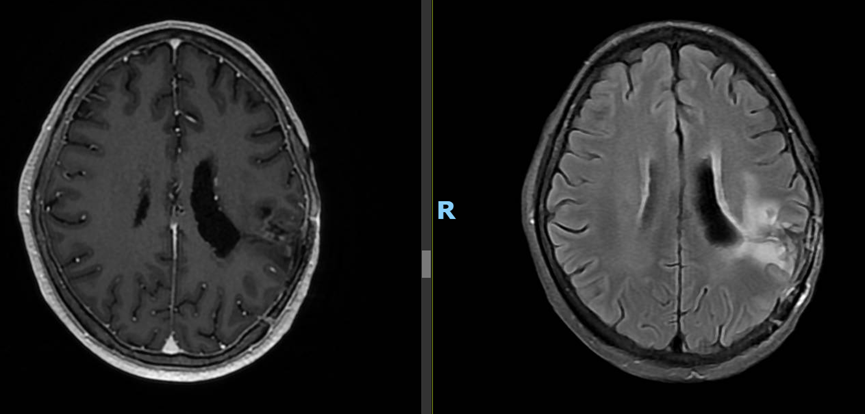

多学科联手,前沿技术护航:脑瘤患者在这里重获希望

三年前,L女士的人生按下了暂停键。那时,她被诊断出腹腔多发性良性肿块。某一线城市最好的三甲医院病理诊断显示是良性肿瘤,在医生建议下,L女士接受了手术切除。但术后病情没有向她期望的方向好转,相反肿瘤进展迅速,医院虽然给予了L女士挽救性放射治疗,但同样治疗效果甚微。经一位银行的朋友介绍,L女士几经辗转来到了和祐医院肿瘤医学中心找到国际肿瘤专家陆嘉德副院长看诊。在复评后,陆嘉德教授意识到情况并不简单,肿瘤的生物分子行为呈现明显的恶性特征,初步断定是恶性肿瘤。陆院长建议立即与美国纪念斯隆-凯特琳癌症